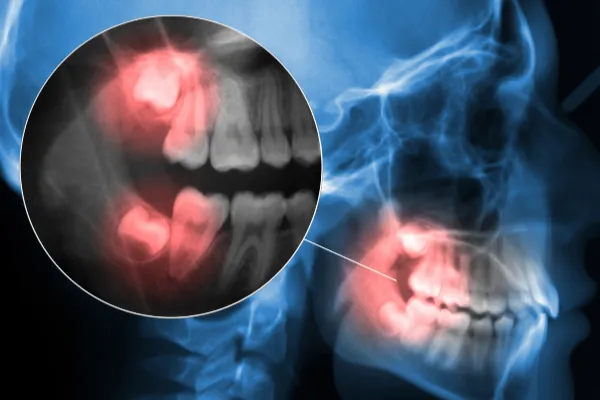

For more complex cases, such as impacted teeth, we may use a minor surgical approach. You can rest easy knowing your care is in expert hands at Cap Dental.

Required for teeth that are broken off at the gumline or impacted.

Prevent future complications from impacted or misaligned third molars.